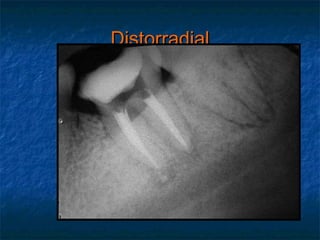

Distorradial.

Regla de Clark ILOV.

Mesiorradial

Inicial

Ortorradial

Distorradial

Mesiorradial. Distorradial. Regla de Clark ILOV.